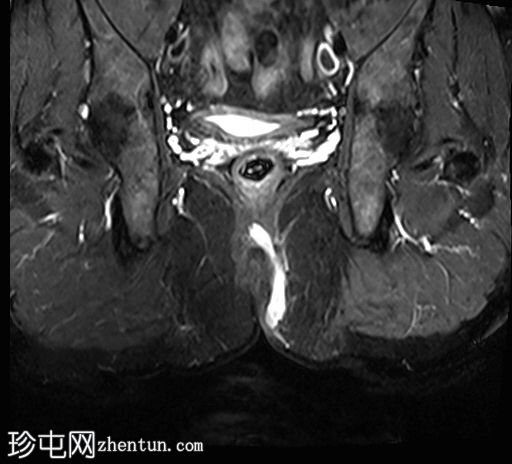

冠状位

T2

位于5点钟和6点钟位置之间,在STIR和T2加权图像上呈高信号。

瘘管起源于括约肌间平面附近,穿过肛门内外括约肌,并延伸至左侧坐骨肛门窝。瘘管内充满液体信号,周围有轻微水肿。肛提肌上方未观察到颅骨延伸。

根据圣詹姆斯大学医院的磁共振分类系统,该病例被归类为III级左侧肛周经括约肌瘘,左侧坐骨肛门窝可见炎症改变。